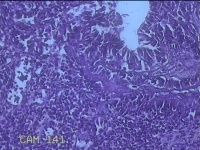

宫颈赘生物

性别

女

年龄

37岁

临床诊断

早期人工流产;宫颈炎性疾病

一般病史

宫颈有1赘生物。

标本名称

大体所见

灰白暗红色肿物1.3x0.8x0.2cm一个,表面糜烂。

息肉,那氏囊肿